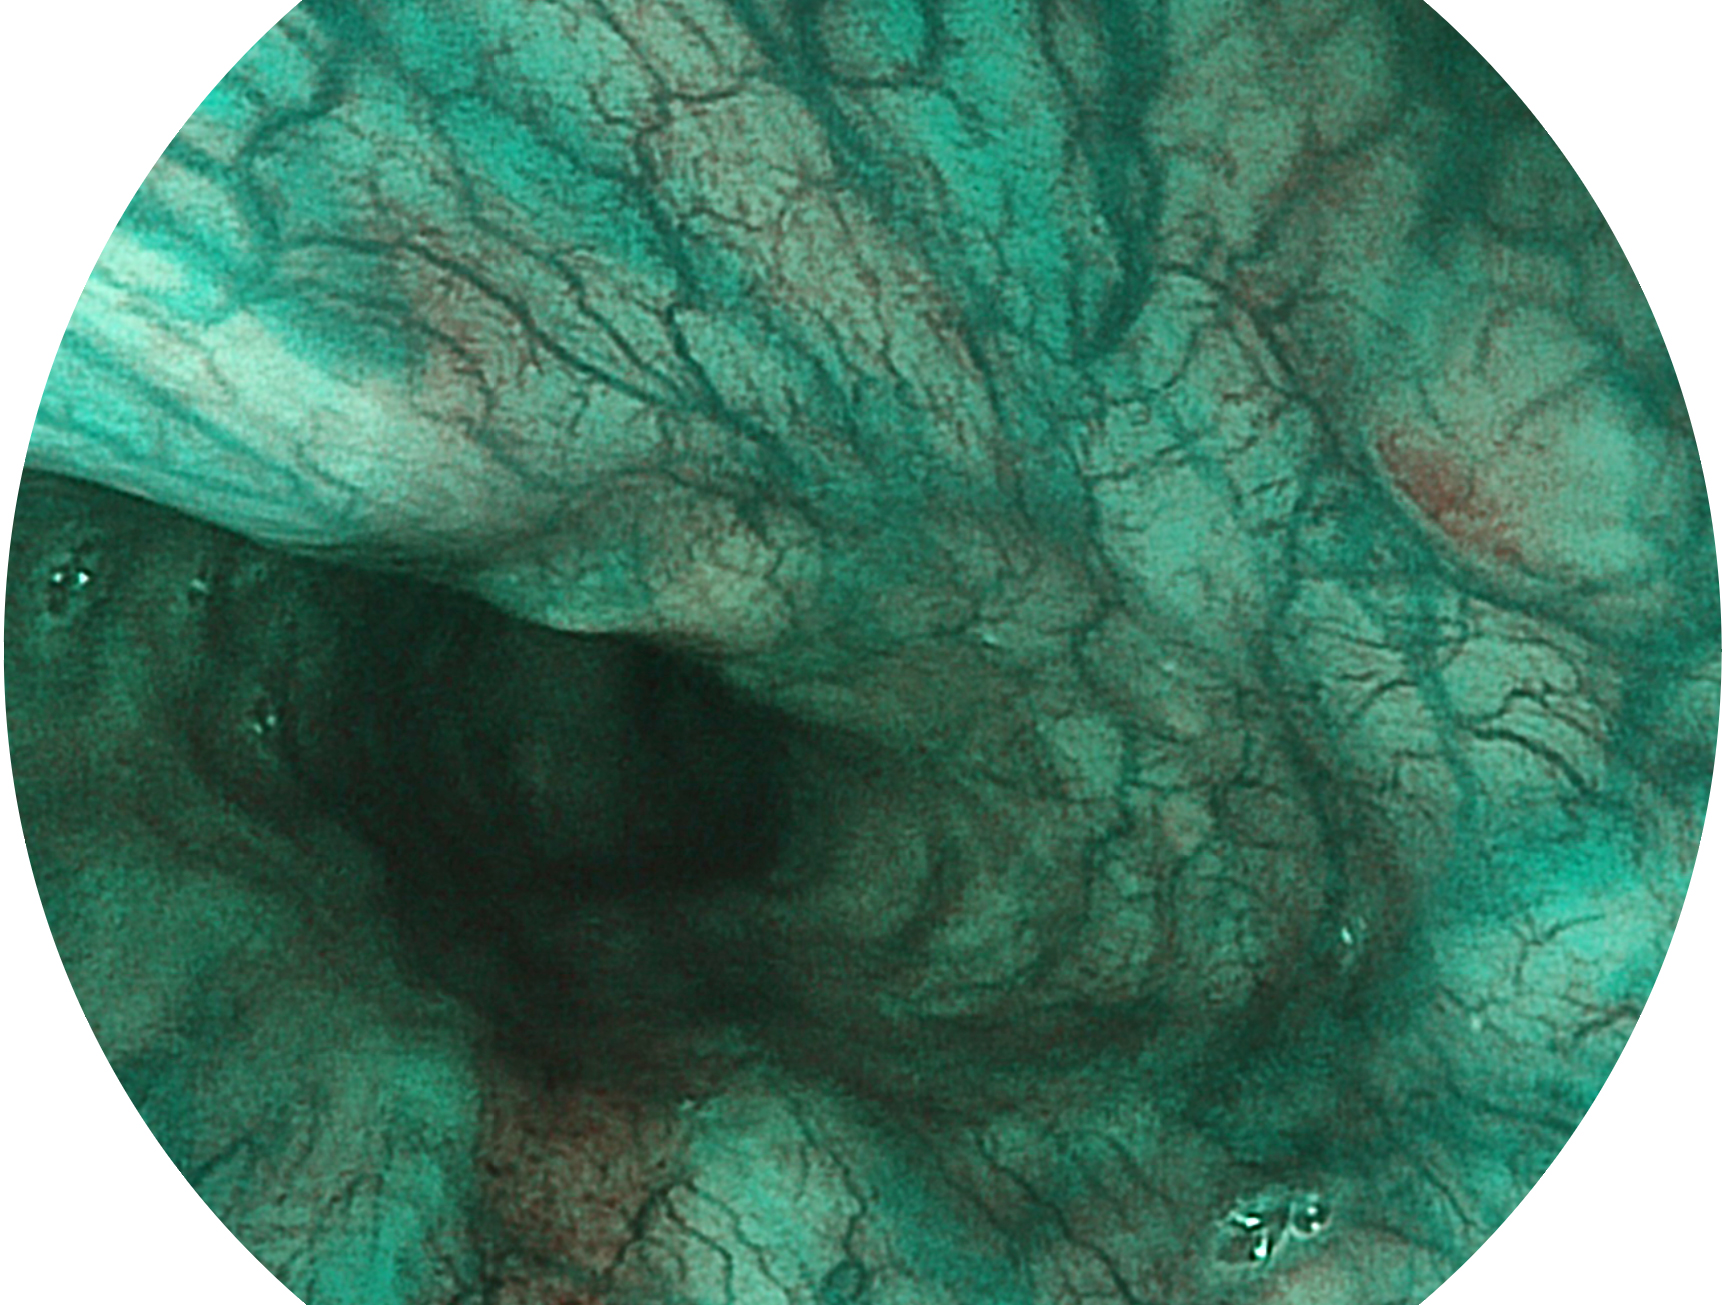

db真人体育官网新开发的内镜染色技术,主要是基于多波长LED 光源的开发,VLS-55Q 四波长LED 光源是由四个不同颜色的LED光按照相应照明模式所规定的特定发光比例进行合束后形成,合束后形成的照明光的光谱由红光、绿光、蓝光及蓝紫光这四个不同的波段范围构成。具有更高光谱自由度,通过光谱比例的控制,实现了聚谱成像技术,英文全称为“Spectral Focused Imaging, SFI”,缩写为“SFI”和光电复合染色成像技术,英文全称为“Versatile Intelligent Staining Technology, VIST”,缩写为“VIST”。